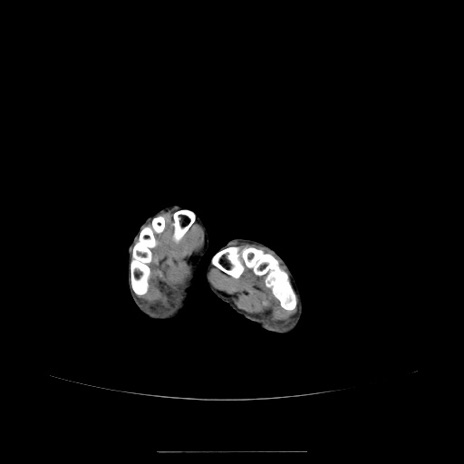

【症例】70歳代女性

【主訴】お腹が張る

【現病歴】1週間くらい前から腹部膨満の自覚あり。昨日夜から増悪したため、本日救急外来受診。

【身体所見】意識清明、BT 36.5℃、BP 165/106mmHg、HR 80bpm、SpO2 98%、腹部:膨満、軟、自発痛・圧痛なし、触診にて不快感あり、腸蠕動音:減弱

【データ】WBC 12600、CRP 1.04